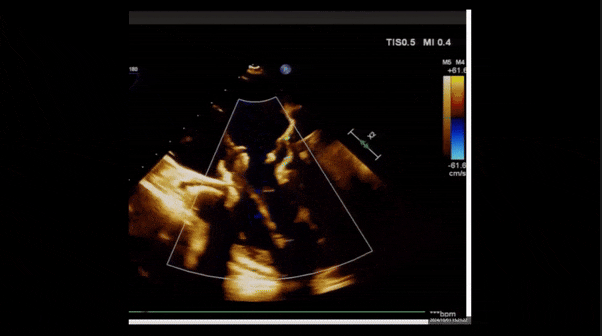

術(shù)后即刻返流

術(shù)后即刻經(jīng)食道超聲可見,三尖瓣假體瓣膜位置合適,牛心包瓣葉運(yùn)動狀態(tài)良好,開閉正常,瓣周及瓣葉對合緣處未見明顯返流,心電圖及心包狀態(tài)較術(shù)前無明顯變化。

術(shù)前術(shù)后返流情況對比